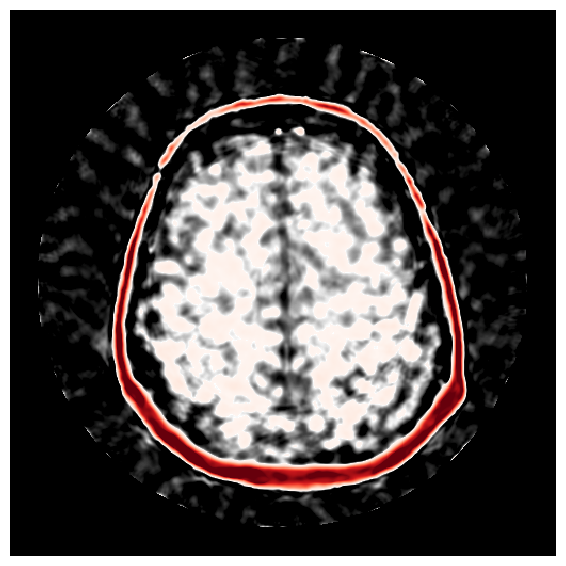

To visualize uncertainty, we calculate uncertainty images by taking the pixel-wise standard deviations as defined in Equation 10 with posterior samples. Figure 12 shows uncertainty images for four iterations of ASPIRE alongside the error of the posterior mean from the ground truth. From these figures, we make the following qualitative observations: (1) uncertainty images increase in resolution with each ASPIRE refinement (2) refinements increase correlations between the uncertainty and the error. Specifically, the errors concentrate near the top and lower-right of the internal brain tissue. The reason being that high acoustic contrast in these areas is creating multiple reverberations of the wavefield inside the brain impeding accurate imaging, importantly these are areas that are highlighted by the uncertainty. Correlations between the uncertainty and the error constitute important empirical evidence of the trustworthiness of the uncertainty. To more rigorously quantify this correlation, and quantitatively validate the uncertainty quantification, we study the calibration of our uncertainty in the following section.